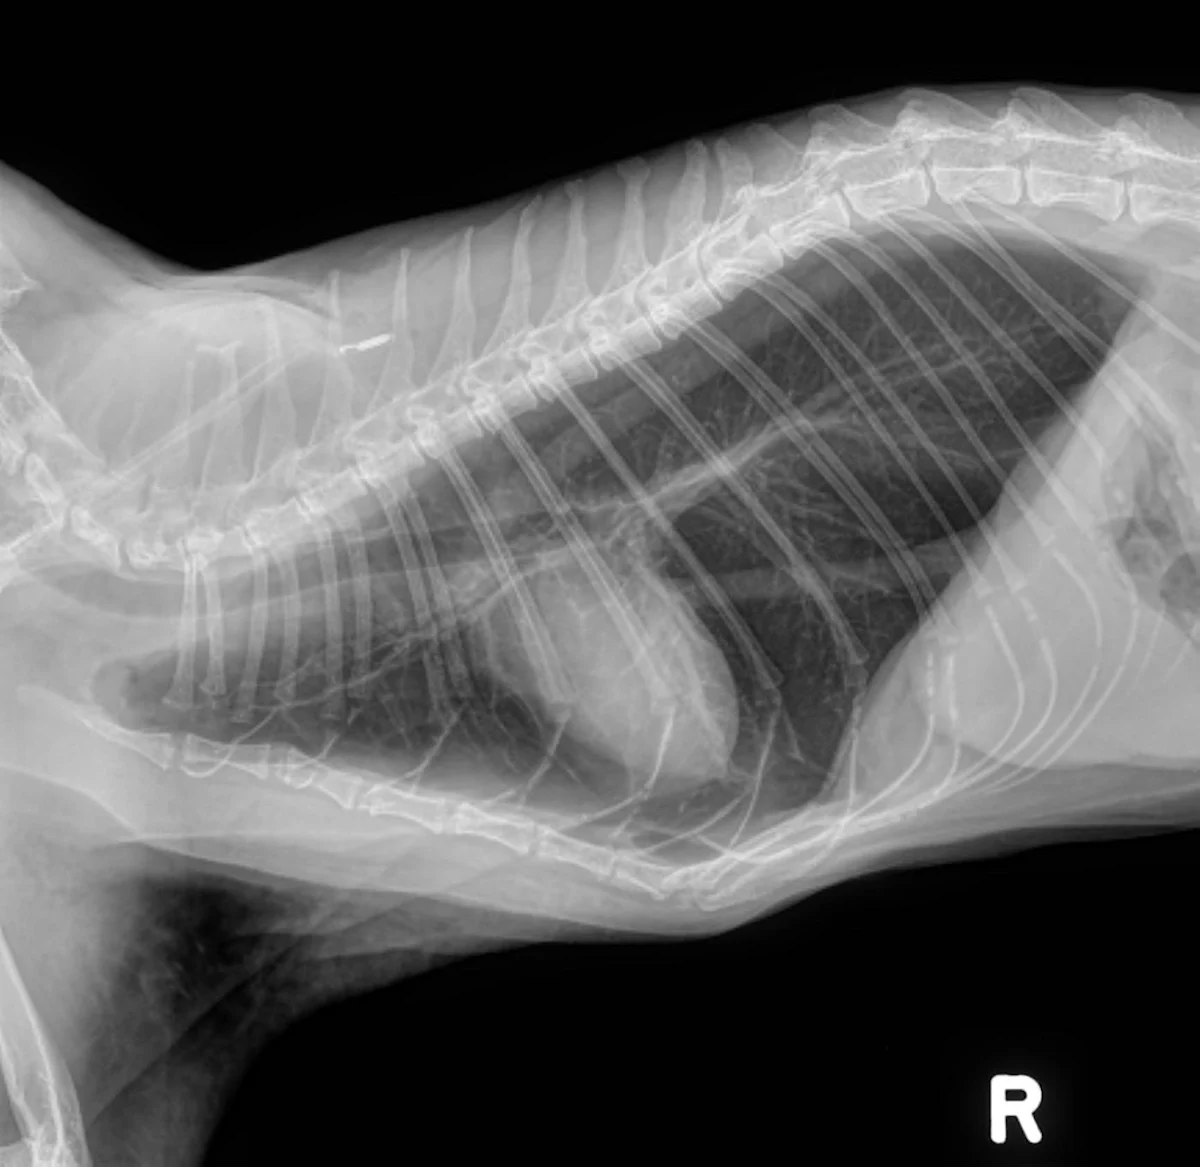

• Thoracic radiographs (3 views): Initial interpretation by overnight doctors was significant elevation of the cardiac silhouette from the sternum (moderate pneumothorax); diffuse bronchial pattern; moderate to severe subcutaneous emphysema of the left axilla. (See Radiographs)

The cat initially presented with a fever and lethargy; then developed acute dyspnea while hospitalized. The diagnosis and decision to treat for pneumothorax was an unfortunate misstep. The films taken upon referral are consistent with a bronchial pattern and show evidence of overinflation. Lung tissue is present throughout all lung fields and, although the cardiac silhouette is elevated, this is due to air trapping within the alveoli and not a pneumothorax. In general, a ventrodorsal view is good for confirming the presence of a pneumothorax: there would be black areas where the lung is pulled away from the chest wall as a result of air in the pleural space. In these films, lung tissue can be seen all the way to the edges of the thoracic cavity. As a side note, spontaneous pneumothorax has been reported in asthmatic cats, so it is not out of the realm of possibility.1

Radiographic Interpretation

Pneumothorax was diagnosed here based on the elevation of the heart from the sternum, which can be one of the signs of pneumothorax. However, it is extremely important to look at the entire radiograph.  In these, (see images) the lung fields can be followed to the edge of the chest cavity on both the lateral and ventrodorsal views: there is no air surrounding the lung lobes. Although the heart looks raised, the area ventral to the heart on the lateral images shows a soft tissue opacity (possibly fat), not air. The lungs are hyperinflated, which is consistent with primary lung disease and not a typical sign of pneumothorax.